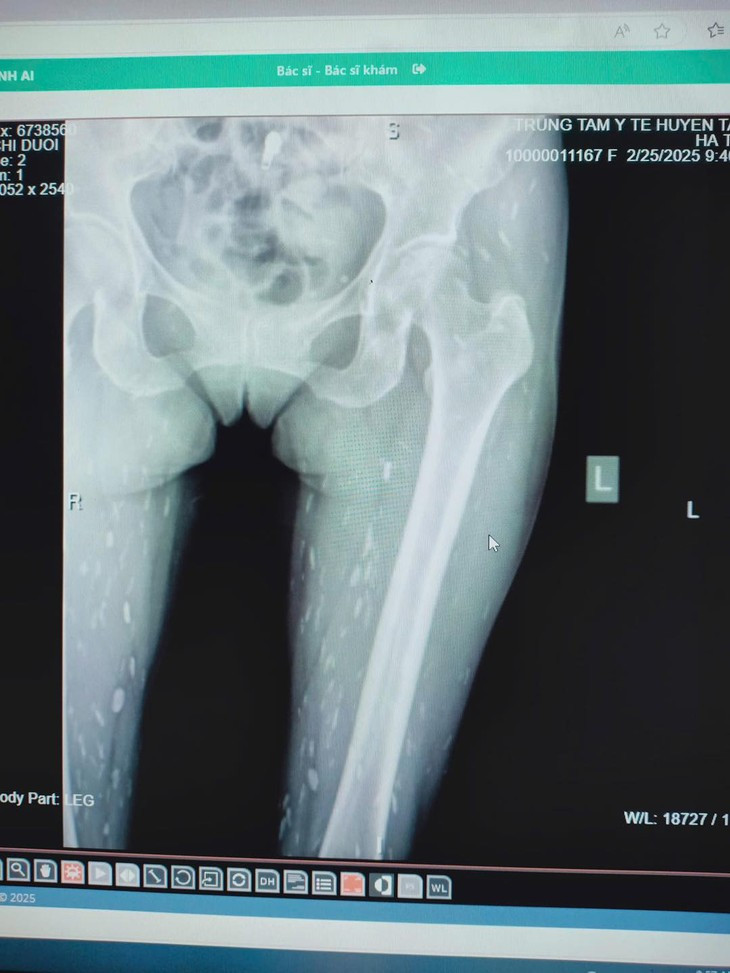

| Nhiễm sán do thói quen thích ăn đồ sống. Ảnh Trung tâm Y tế huyện Tân Sơn |

Ngoài ra, ấu trùng sán còn gây bệnh ở nhiều cơ quan khác. Ở mắt, nang ấu trùng có thể nằm trong hốc mắt, mi mắt, trong kết mạc, thuỷ tinh thể, tiền phòng, làm giảm thị lực hoặc bị mù tuỳ theo vị trí của ấu trùng trong mắt.